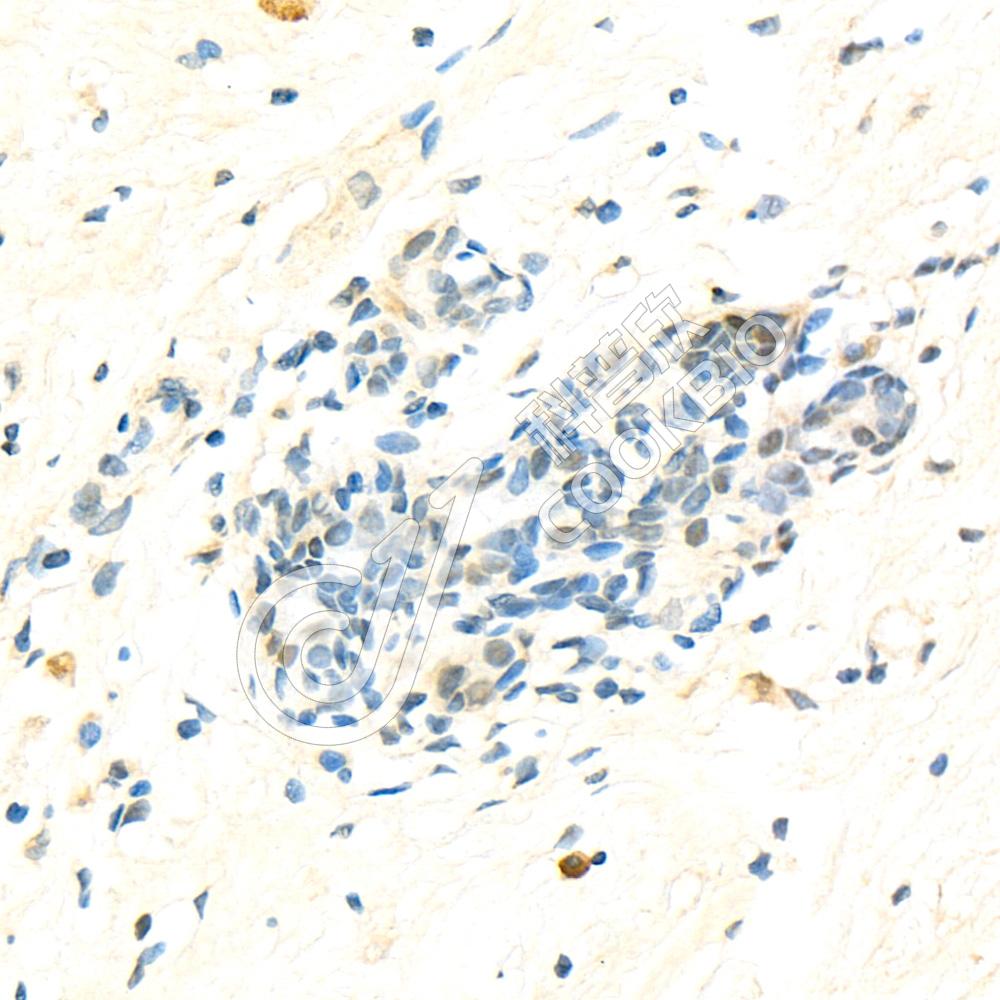

图像

IHC检测ATF-4蛋白(货号 K1333411).

样品: 小鼠骨, 4%多聚甲醛 (货号KSG1101) 固定12-24小时.

抗原修复: 柠檬酸抗原修复液(干粉, pH 6.0) (KSG1201), 98℃, 20分钟.

—抗: 1: 2300稀释, 4℃ 孵育过夜.

二抗: S-vision免疫组化多聚二抗(山羊抗兔),即用型 (货号KB3906), 室温孵育20分钟.